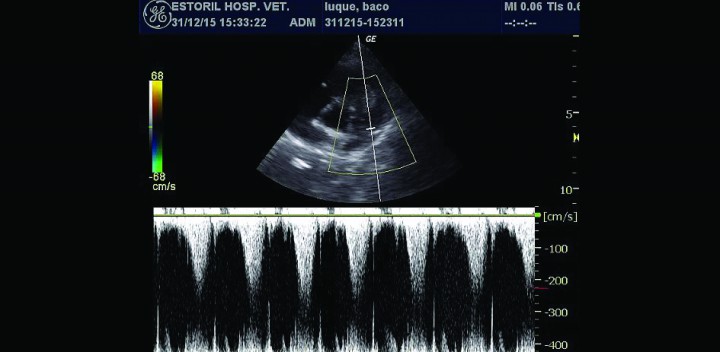

<p>Doppler pulsado arteria pulmonar, flujo acelerado postobstrucción.</p>

Doppler pulsado arteria pulmonar, flujo acelerado postobstrucción.

- Presencia de una masa intraluminal de dos por tres centímetros en tracto de salida derecho (Figs. 3B y 3C), que produce una obstrucción al flujo de salida y, por tanto, una reducción del caudal a través de la arteria pulmonar. El flujo laminar de salida a 1,4 m/s se vuelve turbulento a su paso por la masa, a la que rodea claramente (Fig. 4), provocando una aceleración del flujo hasta los 2,9 m/s (Fig. 5).